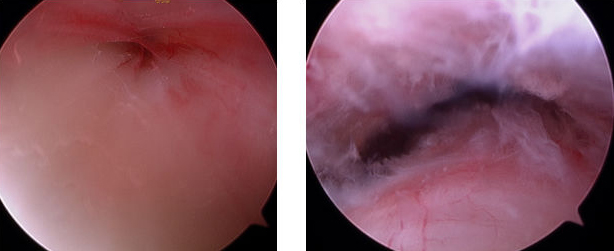

Eine seltene arthroskopische Operation stellt die Behandlung der Achillessehne dar. Häufig werden Problem im hinteren Fußbereich als „Fersensporn“ fehlinterpretiert und somit nicht oder das Problem mit der „falschen“ Therapie behandelt. Probleme in diesem Bereich sind nicht so selten durch die Achillessehne oder deren Begleitstrukturen verursacht und lassen sich in solchen Fällen sehr gut mit dieser minimalen Operationstechnik behandeln.

Intraoperatives Bild einer Sehnenscheidenreizung der Achillessehne vor der operativen Sanierung (links) und nachher (rechts)